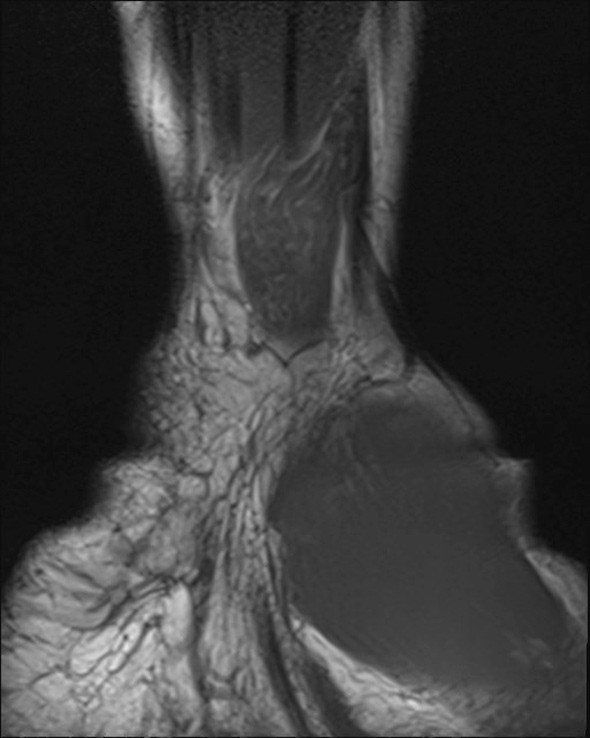

A previously healthy teenage girl was referred to the department of hand surgery with a lump on the flexor side of the left wrist. The lump had been discovered by the girl’s mother around seven years earlier and had gradually become increasingly painful. The patient described hypersensitivity to touch and numbness in the thumb, index, middle and ring fingers. Percussion over the tumour produced radiating pain and increased numbness in the same fingers. MRI showed an enlarged median nerve with a cable-like appearance due to fibrous thickening of the peri- and endoneurium and increased fat separating the roughly 15 nerve fibres (images online). The tumour was approximately 10 cm in size. A lipofibromatous hamartoma was diagnosed on the basis of the MRI findings, which are pathognomonic for the condition (1).

Surgical exploration of the tumour was performed, along with carpal tunnel decompression. At its widest point the tumour (see image) had a diameter three times the size of a normal nerve. At check-ups two and six months later, the patient was still experiencing the same pain as prior to surgery, but sensation in the fingers had improved. Neurography after two months showed moderate axonal and demyelinating sensorimotor neuropathy of the median nerve at the level of the wrist and carpus, suggesting compression neuropathy. EMG examination revealed sparse denervation activity and findings consistent with reinnervation. There were no previous examinations with which to compare the results.